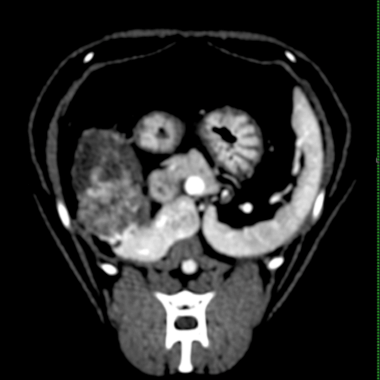

CT(第2病日)

肝動脈尾状葉枝が栄養血管門脈血の流入は確認されず

尾状葉由来5cm大

動脈相

門脈相

CT MIP